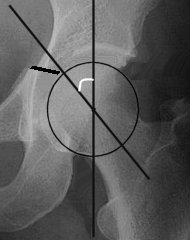

The radiographic roof-arc angle is frequently used to define the weight-bearing

Draw a vertical line through the rotational centre of

the acetabulum

Draw a second line through the rotational centre of the acetabulum

to the point where the fracture crosses the radiographic dome.

The roof-arc angle is the angle

created where these lines cross. |

Matta suggests that a

fracture will cross the weight-bearing dome if the roof-arc angle is less than

45°on any of the three standard radiographic views. Recent biomechanical

evidence suggests that a fracture crosses the weight-bearing area if the

anterior roof-arc is less than 25°, the medial roof-arc is less than 45°, or the

posterior roof-arc is less than 70°.